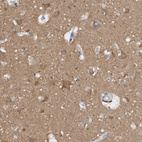

Immunohistochemical staining of human cerebellum shows moderate cytoplasmic positivity in Purkinje cells.